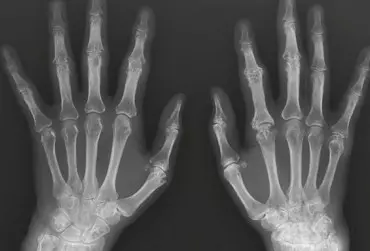

Diagnostyka różnicowa zespołów bólowych kończyny górnej. Część 2

Dolegliwości bólowe w obrębie kończyny górnej mogą mieć różną przyczynę, dlatego tak ważna jest diagnostyka różnicowa. W ustaleniu prawidłowego rozpoznania pomocne jest tradycyjne badanie radiologiczne, które pozwala na wykrycie wielu patologii, takich jak urazy, zmiany zwyrodnieniowe, przeciążeniowe, choroby metaboliczne, zapalne i nowotwory, choć ma też swoje ograniczenia.